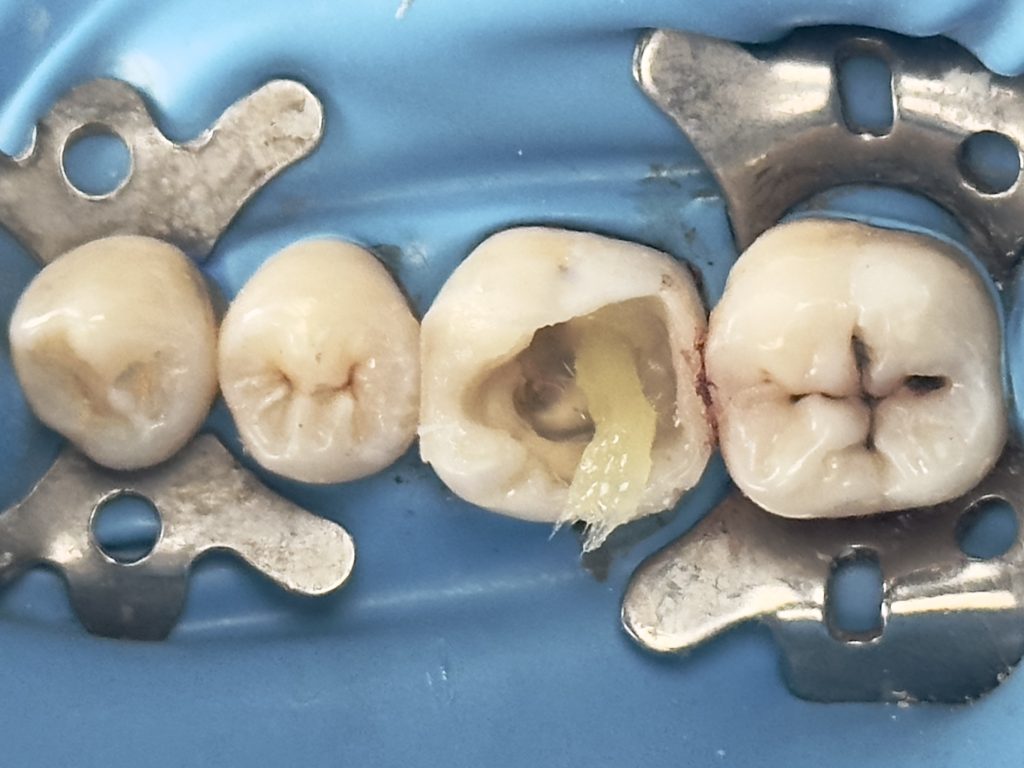

Patient (dentist) came complaining from amalgam restoration placed 3 years ago and caused multiple tooth fractures

1st visit :-

-Complete amalgam removal

-gingival trimming of the inflamed gingival caused by over hanging margin

-clean & neat margin

-IDS & RC

-DME (matrix sealed with teflon &diamond wedge)

-ever X posterior to increase fracture resistance